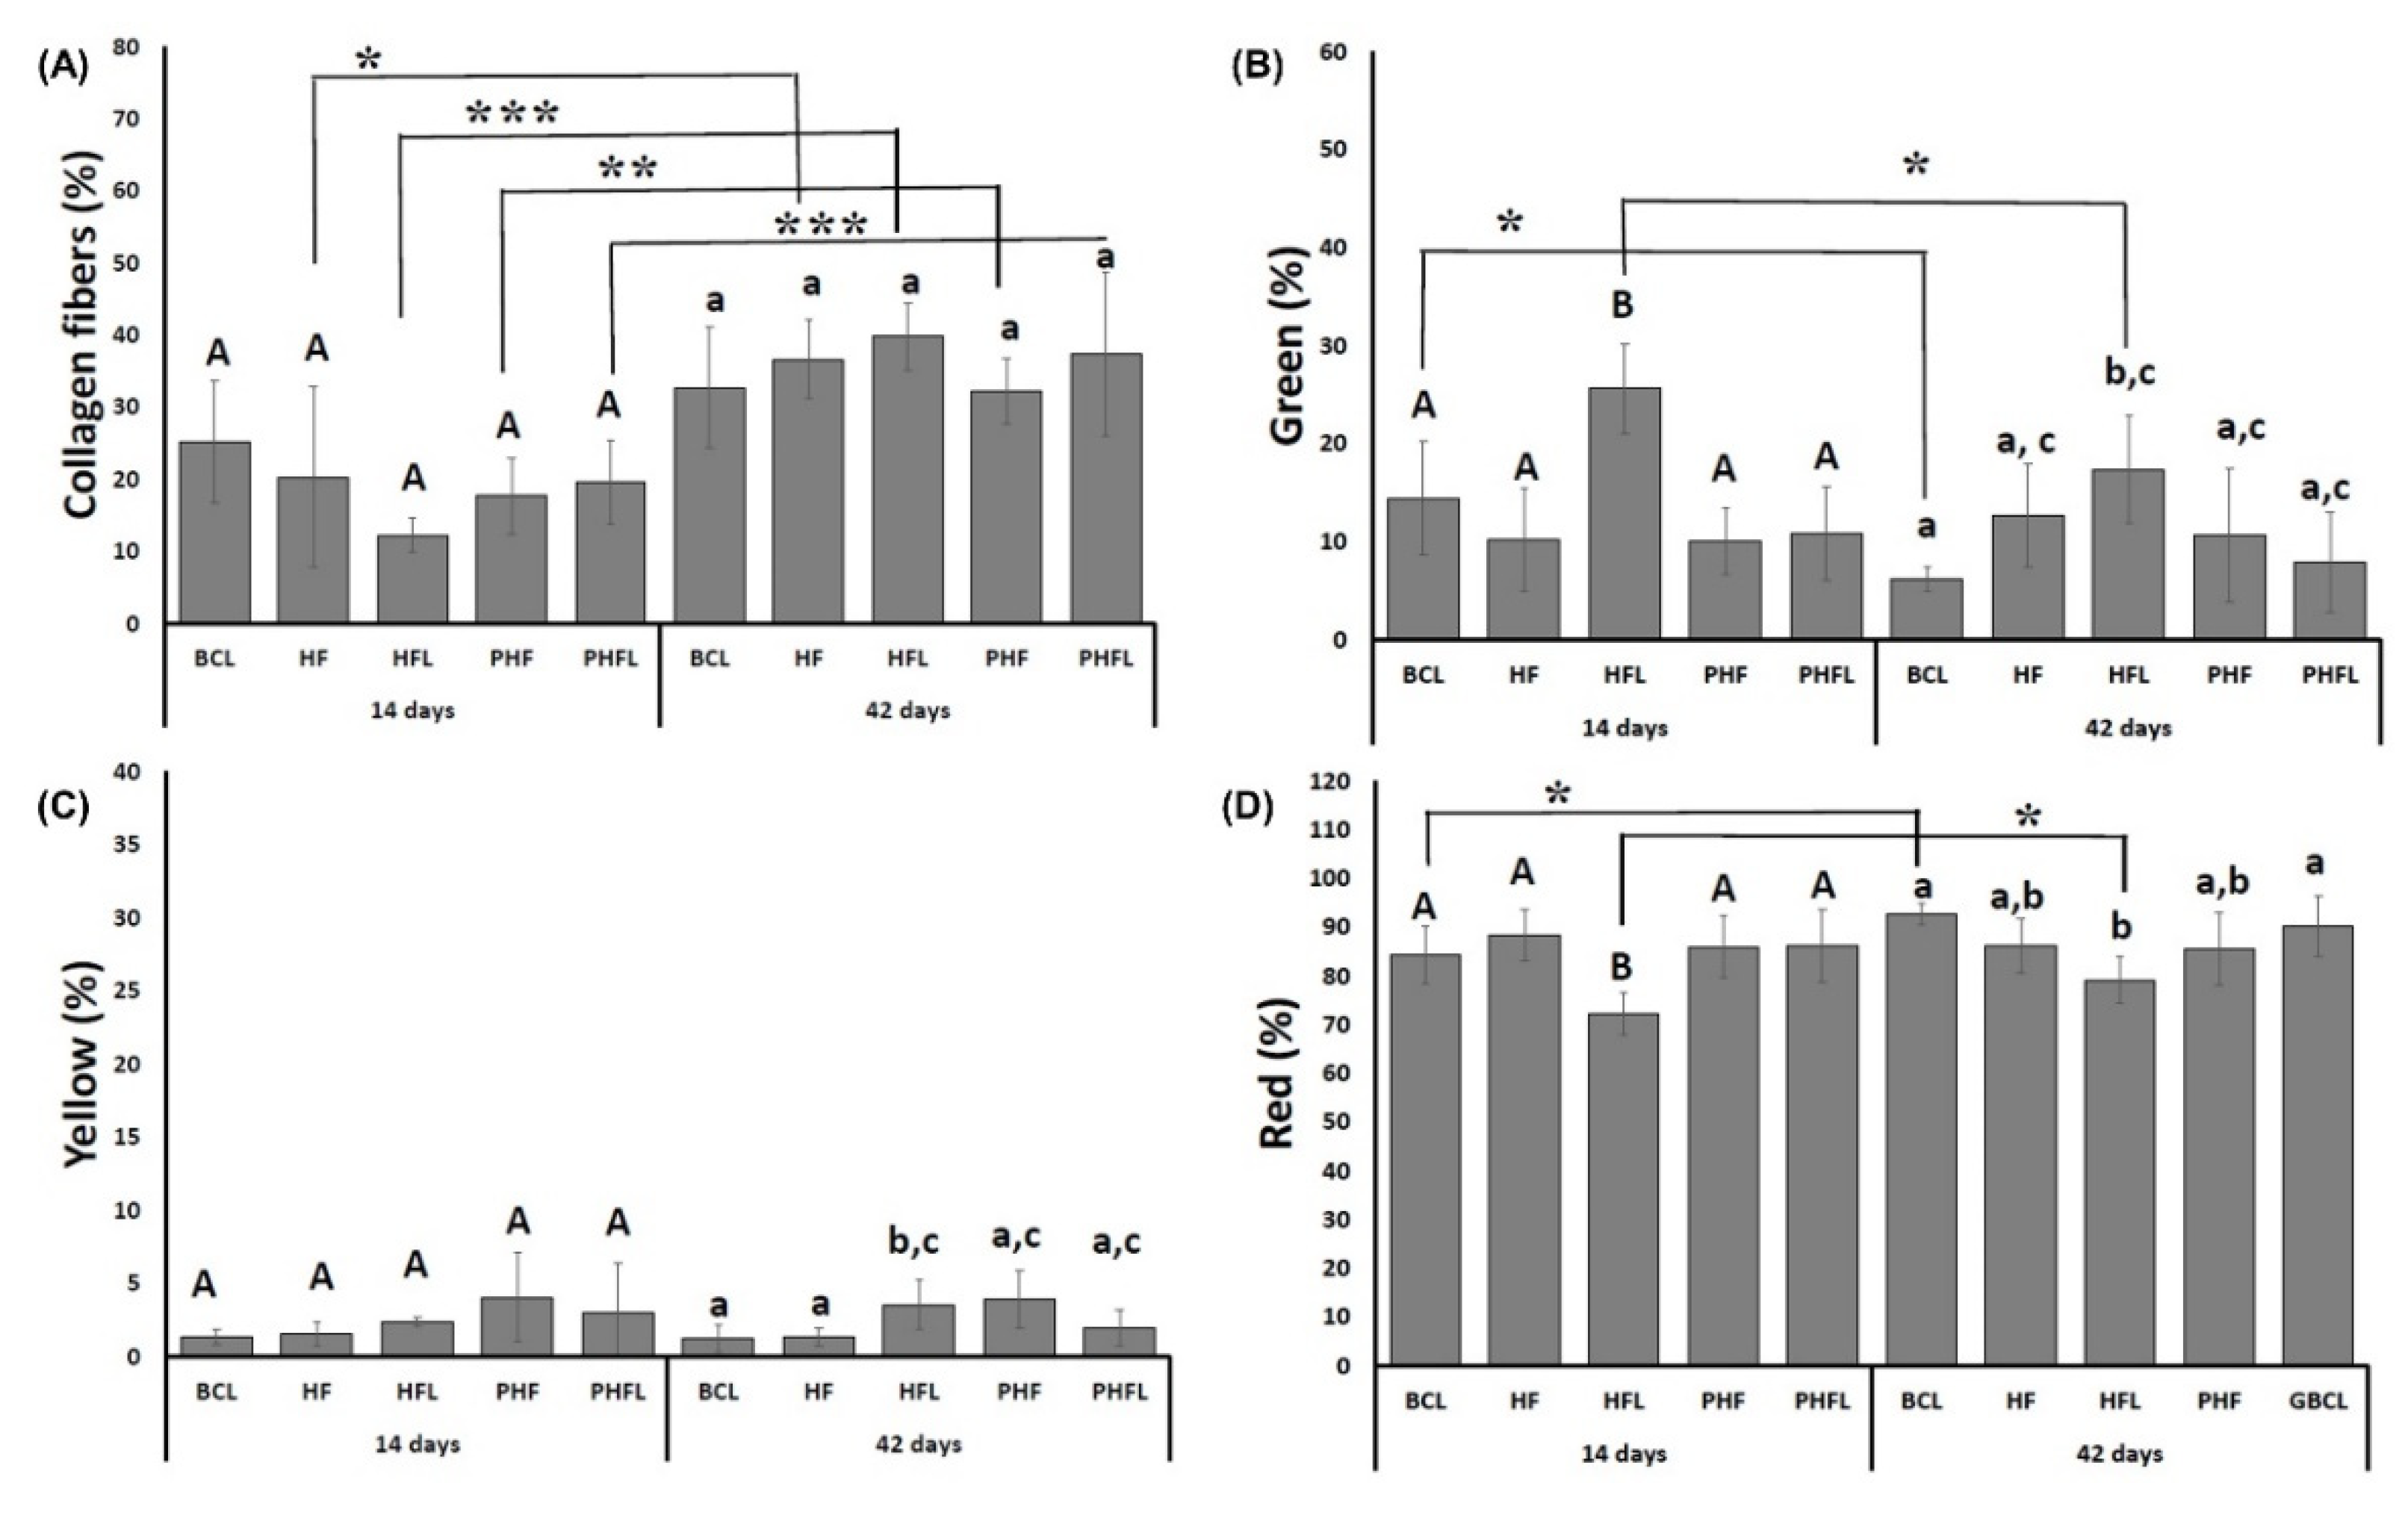

2.3. Birefringence Analysis of Collagen Fibers in Bone Neoformation

4.10. Birefringence Analysis of Collagen Content of Bone Defects

4.11. Statistical Analysis